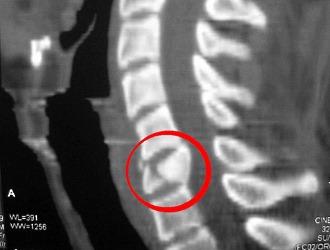

Из-за небольшого количества мягких тканей в области спины, при ушибах основная нагрузка ложится на костную структуру, в частности на позвоночник. Степень тяжести ушиба зависит от того, какой именно отдел позвоночника был поврежден. Ушиб спины проявляется как травмирование мягких тканей или повреждение костной ткани позвоночного столба.

Наиболее часто при ушибах спины страдает позвоночник.

Тяжелая степень ушиба также связана с повреждением позвонков и спинного мозга.

Важно! Независимо от степени тяжести ушиба, даже если клинические проявления уменьшаются, необходимо провести хотя бы рентгеновское исследование для выявления возможных повреждений тканей и позвонков. Даже при легком ушибе могут происходить структурные изменения в тканях, корешках, сосудистой системе и спинном мозге. Отсутствие каких-либо признаков восстановления в течение двух дней после травмы может свидетельствовать о неблагоприятном характере ушиба и плохом прогнозе.